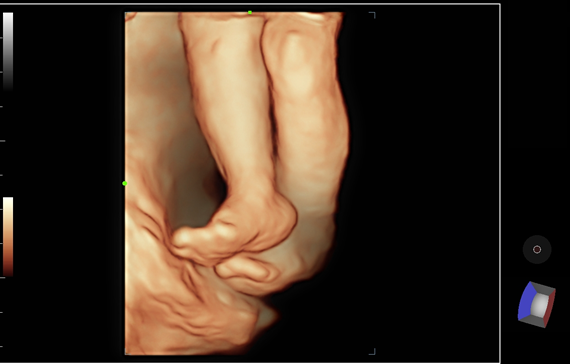

Многофункциональная система ультразвуковой диагностики Mindray DC-60 Exp является одной из ведущих установок высокого класса. Постоянно развиваясь, эта система сочетает в себе стремление к неограниченным возможностям и желание заглянуть в будущее.